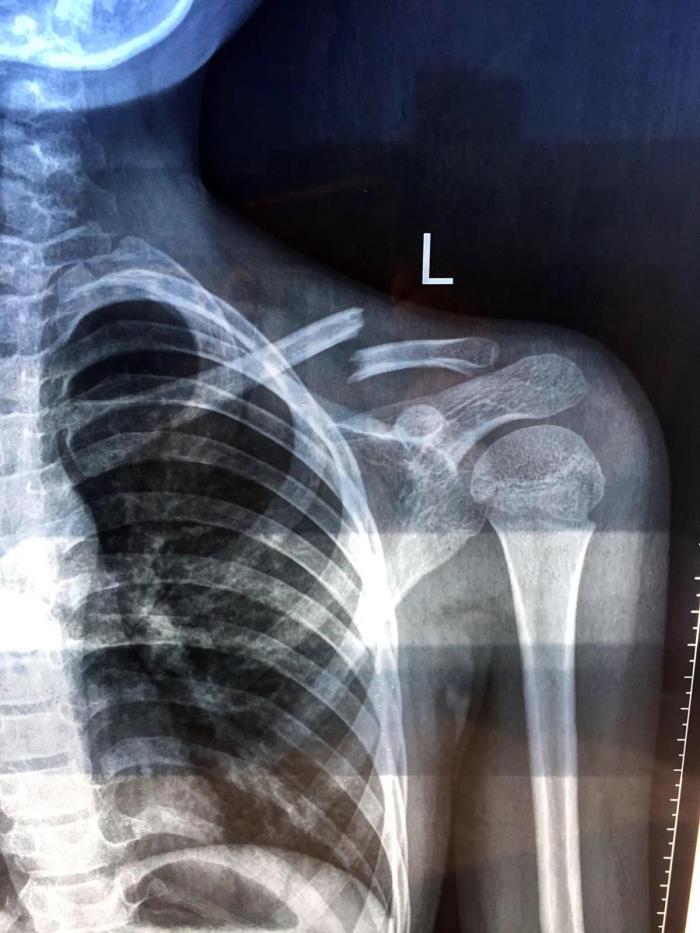

他却不知道,哥哥上体育课不小心摔伤了

让人心疼的小哥哥

好在及时做了手术⚕️

哥哥在医院度过了难熬的又一天☹️